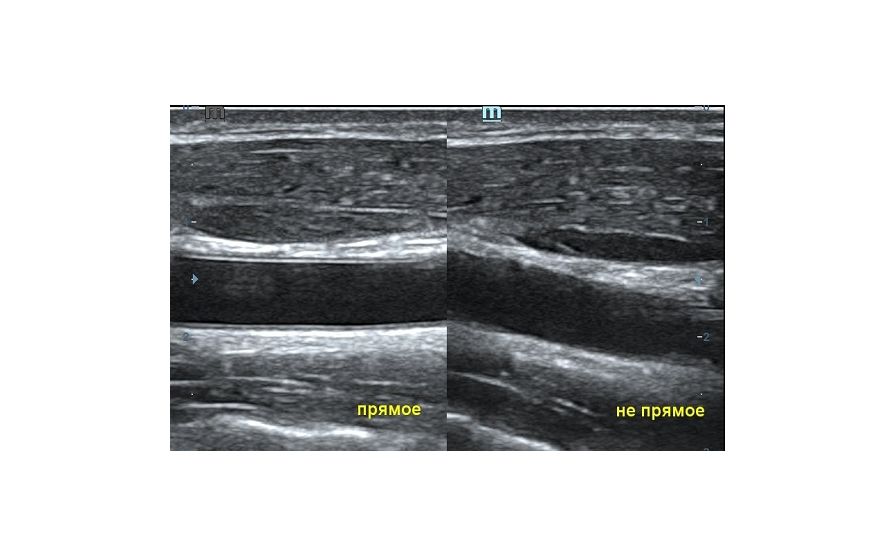

Ультразвуковая волна распространяется от пьезокристалла в направлении плоскости сканирования. Если волна отражается от поверхности исследуемой структуры под прямым углом и возвращается к пьезокристаллу напрямую, на сонограмме появляется четкая дифференцировка структуры и подчеркнутые контуры. Прямое отражение - самый важный критерий техники сканирования для измерения точных размеров органа. В случае отражения волны не под прямым углом эхогенность структуры меняется, дифференцировка на слои падает, контуры становятся нечеткими. Таким образом косой срез дает огромную погрешность измерения и затрудняет описание эхоструктуры объекта.

Как достичь прямого отражения Достаточно расположить объект на экране горизонтально, с помощью наклона датчика, чтобы волна отражалась от поверхности под прямым углом. При любом типе исследования любого органа или системы прямое отражение – залог достоверных результатов.